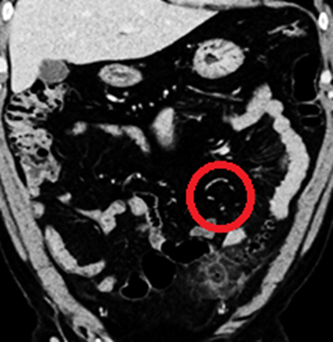

6. A contrast-enhanced CT scan of the abdomen and pelvis was performed for further evaluation.

Quiz

1. What is the key CT finding?

Explanation: Of the options listed, microperforation is the sole finding demonstrated on the CT scan. There is no radiologic evidence of bowel obstruction, free intraperitoneal air, or abscess formation.

Findings and Diagnosis

CT scan: Diverticula are seen in the proximal sigmoid colon, demonstrating mild mural thickening and adjacent fat stranding along the anterior aspect. An inflamed diverticulum with localized contrast enhancement is noted, consistent with acute diverticulitis with localized microperforation.

Multiple small gas foci arranged in a linear pattern were observed within the adjacent mesentery, surrounded by inflammatory changes, suggestive of microperforation without abscess formation. A portion of the distal ileum appeared mildly dilated, likely representing reactive localized ileus rather than true small bowel obstruction.

Diagnosis

Acute sigmoid diverticulitis with localized microperforation (Uncomplicated)